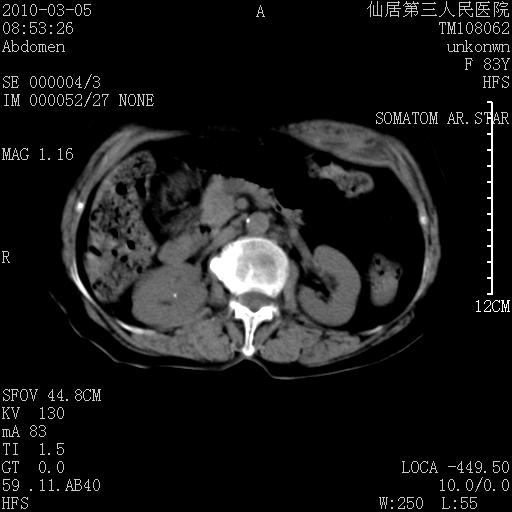

标题: CT24879:腹直肌病变。在线等。

女性,83y,腹痛一周。

考虑:左侧腹直肌神经纤维瘤可能

考虑左侧腹直肌血肿,肿瘤性病变待排。

增强看看,mfh可能性大,次之可考虑血肿、bfh、转移瘤、神经纤维瘤、侵袭性韧带样纤维瘤等。肝内钙化灶,右肾结石。